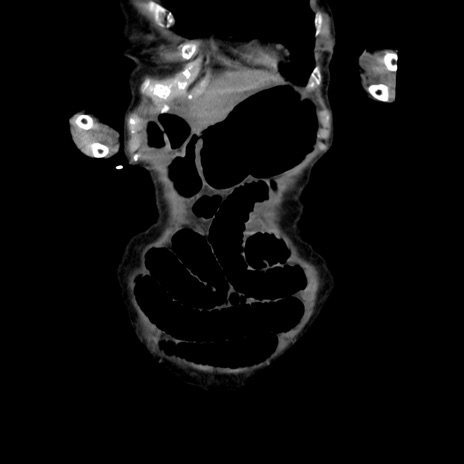

横断像

【症例】80歳代女性

【主訴】嘔吐、腹痛

【現病歴】数時間前より嘔吐あり。心窩部痛出現し、徐々に右下腹痛あり。その後も数回嘔吐あり救急搬送となる。

【既往歴】左大腿骨頚部骨折手術

【身体所見】腹部は膨隆しているが軟らかく圧痛なし。腸雑音はやや亢進。

【データ】WBC 12000、CRP 19.05